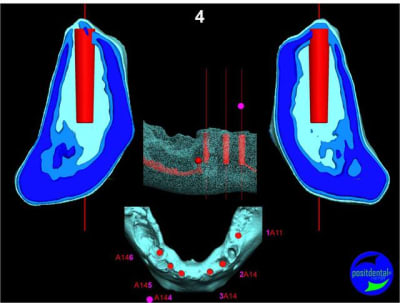

Extraction, pose d’implants Ankylos, pose des piliers Standard définitifs, mise en charge immédiate bi-maxillaire en une chirurgie.

Maxillaire inferieur – extraction 35, 34, 44, 45, 6 implants MCI, comblement osseux, bridge provisoire sans fausse gencive avec renfort métallique.

3D

Préopératoire

uniquement le scan pré-op

en attendant la pano voici les coupes de la S.I.A.O.

bien...mais dans certaines zones,surtout postérieures, j'aurais mis plus gros...surtout qu'il y a la place...